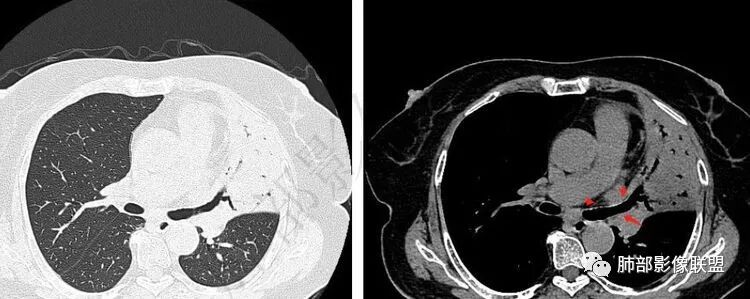

影像特点支持结核。气促、左上肺病灶似乎不能解释I型呼吸衰竭加上D—二聚体明显升高、肺动脉干增粗,临床需要想到二元可能:肺结核合并肺栓塞可能,需要完善CTPA明确有没有肺栓塞,因为急性肺栓塞是急危重症。

1.老年女性,胸闷、气促半个月入院。无发热、咯血、胸痛等。

既往糖尿病病史。双下肢凹陷性水肿。

降钙素高,D-二聚体升高,结核感染T细胞检测阳性。呼衰。

2.纵隔左移。肺动脉增宽。

2.“胸闷、气促”以及呼衰的临床表现,难以以当前肺部的病灶加以解释。

D-二聚体升高,肺动脉成像等明确患者肺栓塞的存在!